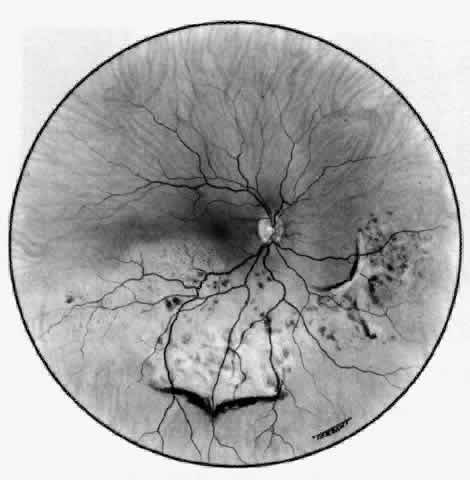

Posterior Scleritis

Because the posterior sclera is invisible, the diagnosis of posterior scleritis is made only if the anterior sclera is also involved or some other sign or symptom leads one to suspect it. Posterior scleritis is much more common than previously suspected, as recent clinical and pathologic studies have shown.19,28,29 There are two distinct forms of posterior scleritis. The first is usually associated with an anterior scleritis. This granulomatous disorder, like its anterior counterpart, can be diffuse, nodular, or necrotizing in character and is associated with the connective tissue diseases. The second form occurs in young patients of all races who are 9 to 40 years of age. It is always diffuse in character but is not associated with any systemic disorder. Both forms may cause uveitis if the inflammation affects the ciliary body, and in both forms the patient may develop exudative retinal detachments, choroidal folds, and swelling of the disc (Figs. 51 and 52). The granulomatous type may also involve the structures outside the globe, causing proptosis (Fig. 53), limitation of ocular muscle movement, and, uniquely, retraction of the lower lid on attempted elevation of the eye (Fig. 54). Diagnosis is with B-scan ultrasonography.

Fig. 51. Swelling of the optic nerve head and hemorrhage near the disc in a patient with posterior scleritis. The poor quality of the photograph is partly due to vitreous haze that accompanied the inflammation.

Fig. 52. Fundus appearance after resolution of exudative detachment in patient with severe posterior scleritis. Macula was affected and vision much impaired. (Watson PG: Management of scleritis. In: Recent Advances in Ophthalmology, Vol 5. London, Churchill-Livingstone, 1975)